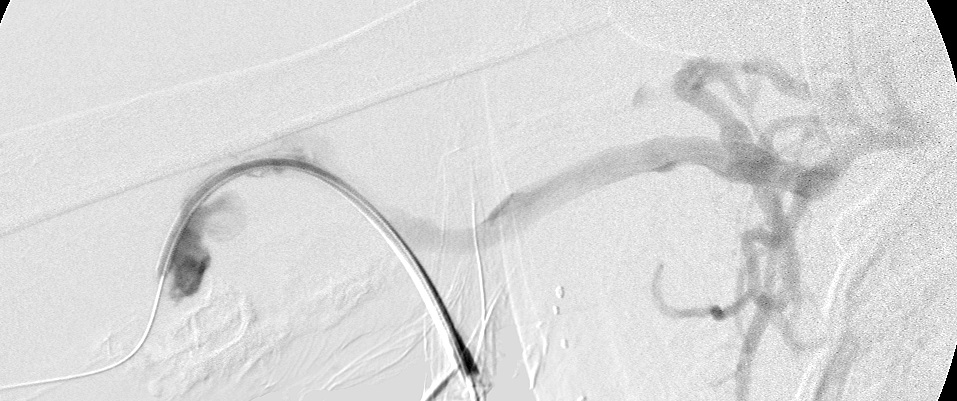

Right brachial venogram during intervention showing collaterals bypassing subclavian stenosis.